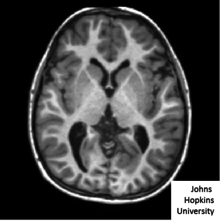

The images in Computational anatomy such as MR images or DTI images are denoted , and are dense functions are scalars, vectors, and matrices (see Figure showing scalar image).